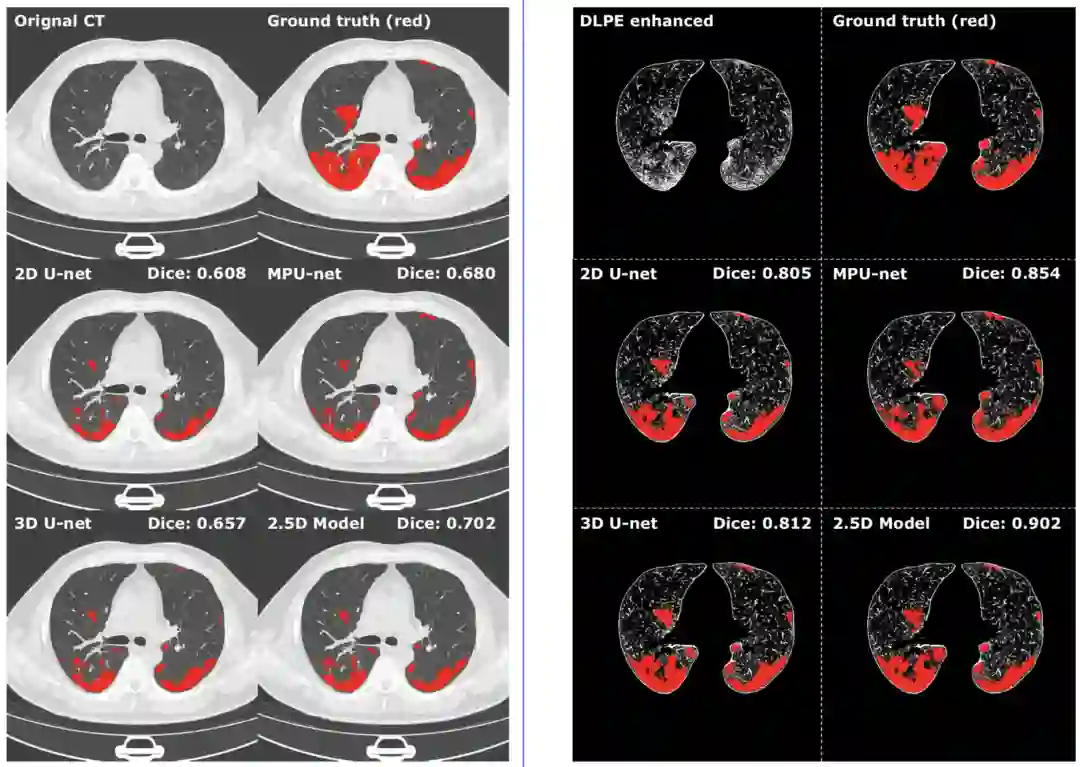

图4,相同ground truth,相同模型下,是否经过DLPE去scan-level bias的区别。左边没有去scan-level bias,右边去掉了,红色区域是肺损伤的标注。可以看到用DLPE去scan-level bias是能成功分割新冠长期肺损伤的关键。